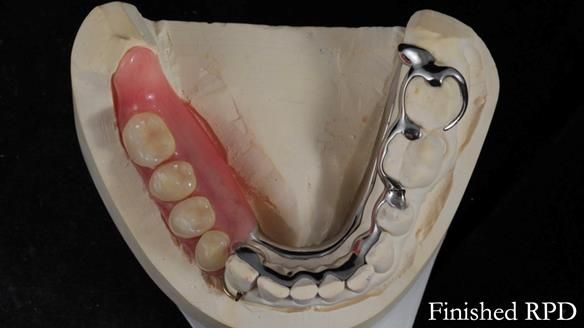

Welcome to Newsletter 61. In this edition, I walk through the process of creating and fitting a metal based lower partial denture for Joyce, a fit and healthy 76 -year-old woman.This issue shows the complete protocol workflow for achieving an exceptionally well-fitted and aesthetically good RPD.

Welcome to Newsletter 61. In this edition, I walk through the process of creating and fitting a metal based lower partial denture for Joyce, a fit and healthy 76 -year-old woman.

The missing lower right teeth to be replaced with a metal based partial denture.

The detailed clinical situation and treatment process are outlined below, with clinical work provided by me and technical work by Rowan Garstang. The treatment spanned six visits for denture fitting and one review.